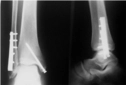

Ayak ezilmesi geçiren biri olarak, iyileşme sürecim oldukça zorlu geçti. Şişlik ve ağrı ile başa çıkmak zorundaydım. Genel olarak ayak ezilmesi kaç günde geçer diye merak ediyorum, çünkü bu durumun süresi kişiden kişiye değişiyor gibi görünüyor.

Ayak ezilmesi, gerçekten zorlu bir deneyim olabilir. İyileşme süresi birçok faktöre bağlı olarak değişiklik göstermektedir. Genellikle, hafif ezilmelerde birkaç gün içerisinde iyileşme sağlanabilirken, daha ciddi durumlarda bu süre bir hafta veya daha uzun sürebilir.

Yaş, genel sağlık durumu, yaralanmanın ciddiyeti ve tedavi yöntemleri gibi etkenler iyileşme sürecini etkileyebilir. Ayrıca, dinlenme, buz uygulama ve gerekirse fizik tedavi gibi yöntemler de iyileşme sürecini hızlandırabilir.